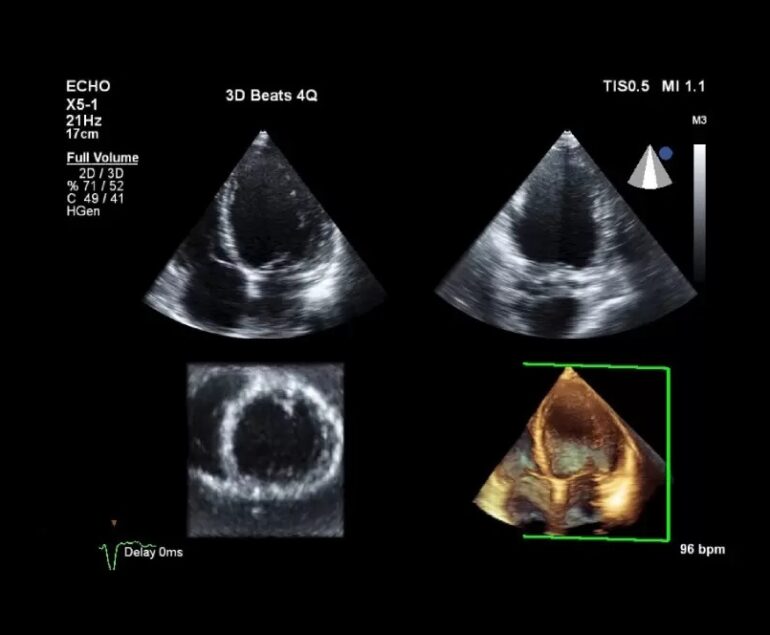

- Rezultate recente: ECG, ecocardiografie, NT-proBNP